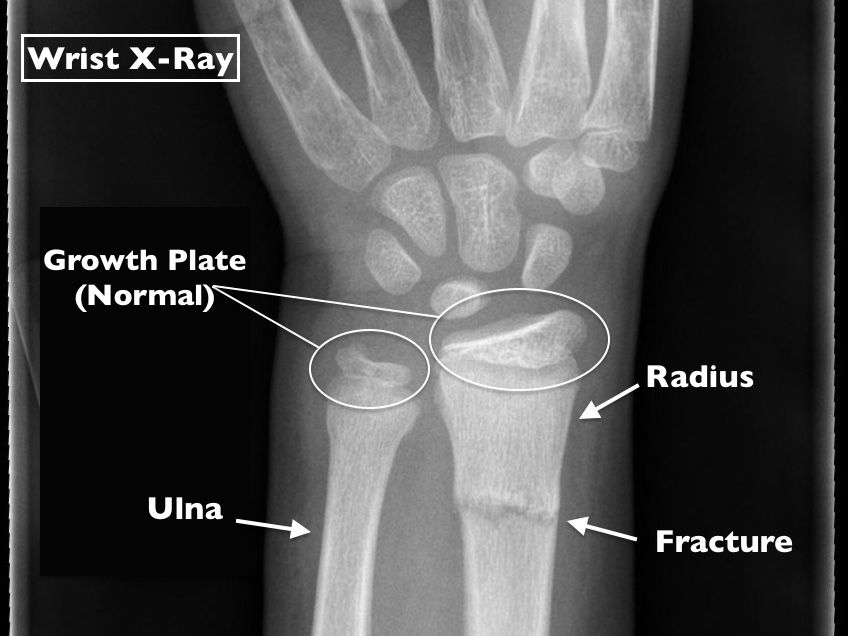

The radius and the ulna. Wrist injuries are common in children and teenagers and are often the result of an overuse injury, sprain or broken bone. The forearm is the part of the arm between the wrist and the elbow.

Overall, for children and adolescents younger than 18 years of age, metacarpal fractures are the most common injuries of the hand and wrist bones. A broken wrist often involves the end of the radius bone, called the distal radius. The most common wrist fracture is a distal radius fracture, when the radius (the larger bone in the forearm) is fractured on the distal end, near the wrist.

Is a legal document that explains the tests, treatments, or procedures that your child may need. Fractures of the distal radius (wrist) are the most common forearm fracture in children. Historically, the distal pole was considered the most frequently fractured portion of the scaphoid in children.

Plus, learn four ways you can help heal a. Most are buckle fractures, which are stable fractures, unlike greenstick and other usually displaced fractures. About three out of four forearm fractures in children occur at the wrist end of the radius.

One or both bones may be broken radius figure 2. Their bones have a different consistency and quality, like soft, fresh wood, as compared to when we. Gholson et al have documented a changing pattern of scaphoid fracture location in children that has become more similar to the adult pattern, with more scaphoid waist injuries.